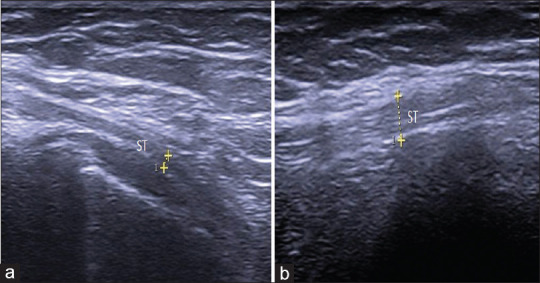

Methods: We studied the distal medial hamstring tendons (semimembranosus [SM] and semitendinosus [ST]) of 104 patients (104 knees) with nontraumatic unilateral PM knee pain and 118 healthy controls (236 knees). U/S evaluations included tendon thickness, echogenicity, the presence of intrasubstance tears, calcifications, and vascularity.

Results: The mean age of patients and controls was 51.7 ± 10.4 years and 49.8 ± 9.9 years, respectively. The mean Visual Analog Scale (VAS) for pain among patients was 5.1, with 58.6% of them reporting pain at the medial joint line. The study patients had significantly higher mean SM and ST tendon thicknesses than the controls (7.17 mm vs. 5.46 mm and 3.93 mm vs. 3.45 mm, respectively). U/S abnormalities among patients were hypoechogenicity (62.5%), intrasubstance tears (31.7%), loss of fibrillar pattern (23.1%), baker cyst (20.2%), calcification (18.3%), anserine bursitis (11.5%), and neovascularization (6.7%). We found significant correlations between tendon thickness and VAS (r = 0.752, P = 0.004) as well as pain location (r = 0.680, P = 0.008). SM tendon thickness measured by U/S was more accurate in predicting tendinopathy than ST (80.6% vs. 68.9%).